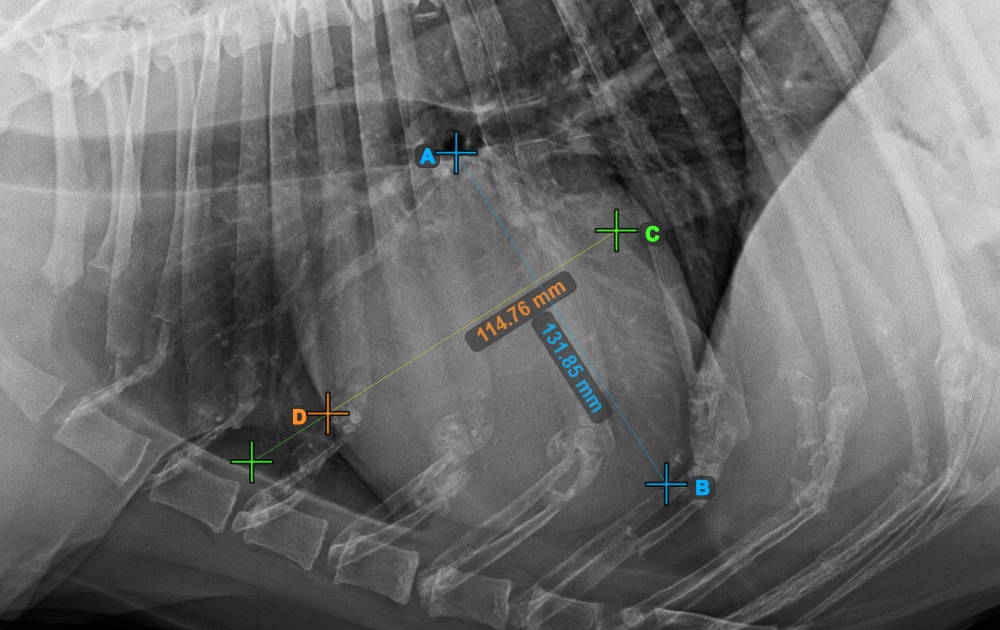

The image below represents a typical placement of the Bifurcatio tracheae point.

../../_images/image393.jpg

Complete the long axis of the heart by marking the Apex point, near the bottom of the heart.

The image below represents a typical placement of the Apex point.